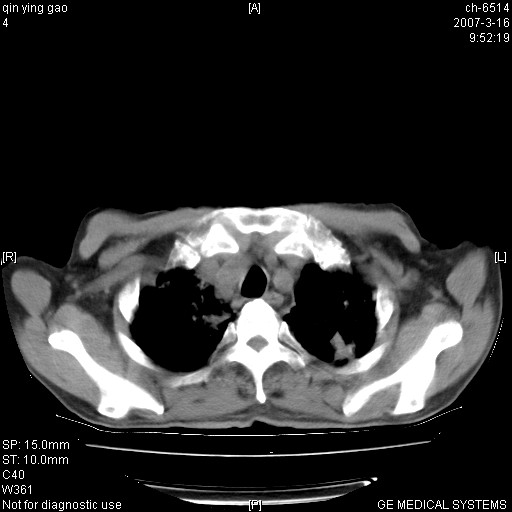

男,64岁.乏力2个月,畏寒、发热1月余。体重下降。血沉加快,白细胞不高。

双肺以中上肺野为著斑片状.结节壮密度增高影 左上肺前段可见小类圆钙化灶 纵隔淋巴结无明显肿大

3.主动脉弓.冠状动脉钙化形成

双肺以中上肺野为著斑片状.结节壮密度增高影,纵隔淋巴结无明显肿大。考虑:

双肺以中上肺野为著斑片状.结节壮密度增高影 左上肺前段可见小类圆钙化灶 纵隔淋巴结无明显肿大1.肺结核2.支气管肺泡癌待排

两肺弥漫分布的斑片状影,部分融合,左肺及纵隔淋巴结见钙化影,考虑1。tb,2。肺泡细胞癌,建议查痰检

病变以两肺上野为著,部分病灶有钙化,纵隔窗显示病灶有新老不一,这个首先和结核脱不了干系,还有部分病灶有融洽的倾向,肿瘤也不能完全排出